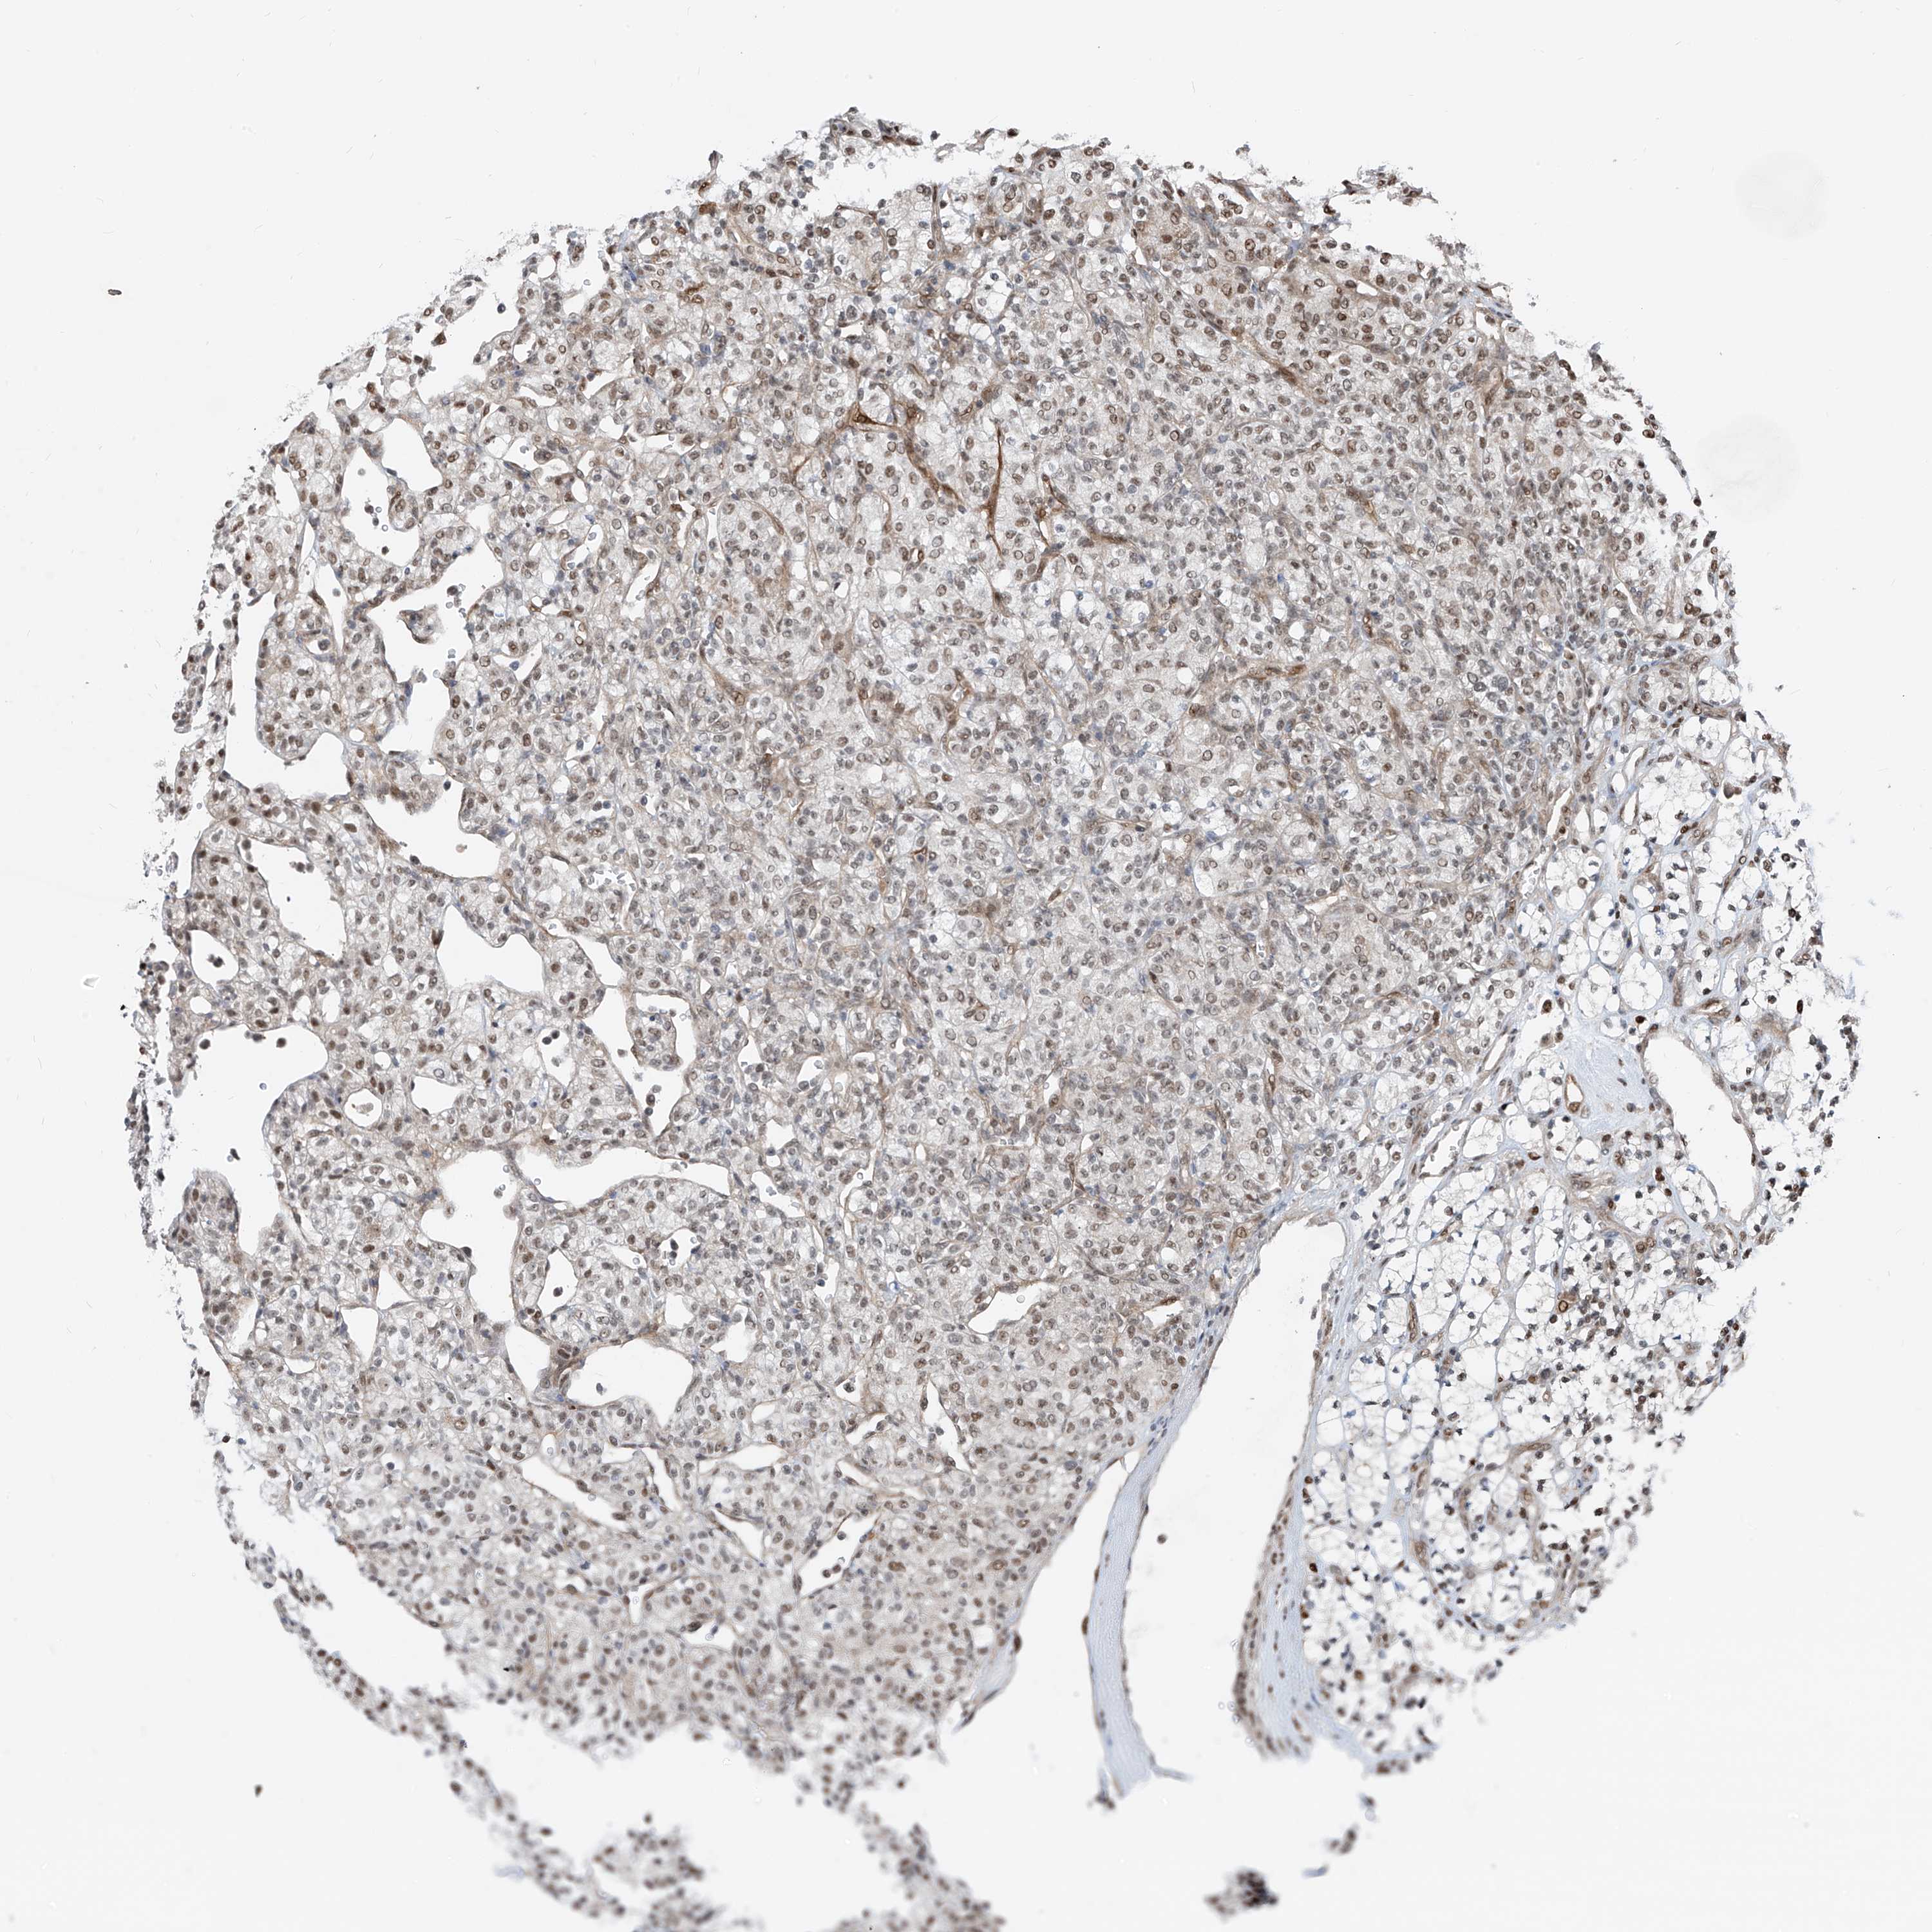

KIDNEY RENAL CLEAR CELL CARCINOMA (TCGA) - Interactive survival scatter ploti

The Survival Scatter plot shows the clinical status (i.e. dead or alive) for all individuals in the patient cohort, based on the same data that underlies the corresponding Kaplan-Meier plots. Patients that are alive at last time for follow-up are shown in blue and patients who have died during the study are shown in red.

The x-axis shows the expression levels (FPKM) of the investigated gene in the tumor tissue at the time of diagnosis. The y-axis shows the follow-up time after diagnosis (years). Both axes are complimented with kernel density curves demonstrating the data density over the axes. The top density plot shows the expression levels (FPKM) distribution among dead (red) and alive patients (blue). The right density plot shows the data density of the survived years of dead patients with high and low expression levels respectively, stratified using the cutoff indicated by the vertical dashed line through the Survival Scatter plot. This cutoff is automatically defined based on the FPKM cutoff that minimizes the p-score. The cutoff can be changed by dragging the vertical line or by entering a cutoff value in the square labeled "Current cut-off".

Under the Survival Scatter plot the p-score landscape (black curve; left axis) is shown together with dead median separation (red curve; right axis). Dead median separation is the difference in median mRNA expression between patients who have died with high and low expression, respectively. It is calculated as follows: median FPKM expression of dead patients with high expression - median FPKM expression of dead patients with low expression. This is intended to aid the user in visually exploring custom cutoffs and the associated p-scores and dead median separation.

Individual patient data is displayed and can be filtered by clicking on one or more of the category buttons on the top of the page. Categories describing expression level and patient information include: high, low, alive, dead, female, male and tumor stages. The scale of the x-axis can be toggled between linear and log-scale by clicking on the "x log" button. Mouse-over function shows TCGA ID, patient information and mRNA expression (FPKM) for each patient.

& Survival analysisi

Kaplan-Meier plots summarize results from analysis of correlation between mRNA expression level and patient survival. Patients were divided based on level of expression into one of the two groups "low" (under cut off) or "high" (over cut off). X-axis shows time for survival (years) and y-axis shows the probability of survival, where 1.0 corresponds to 100 percent.

RBP7 is validated prognostic, high expression is favorable in Kidney Renal Clear Cell Carcinoma (TCGA)

: 44.67

Average pTPM 92.6

Number of samples 521